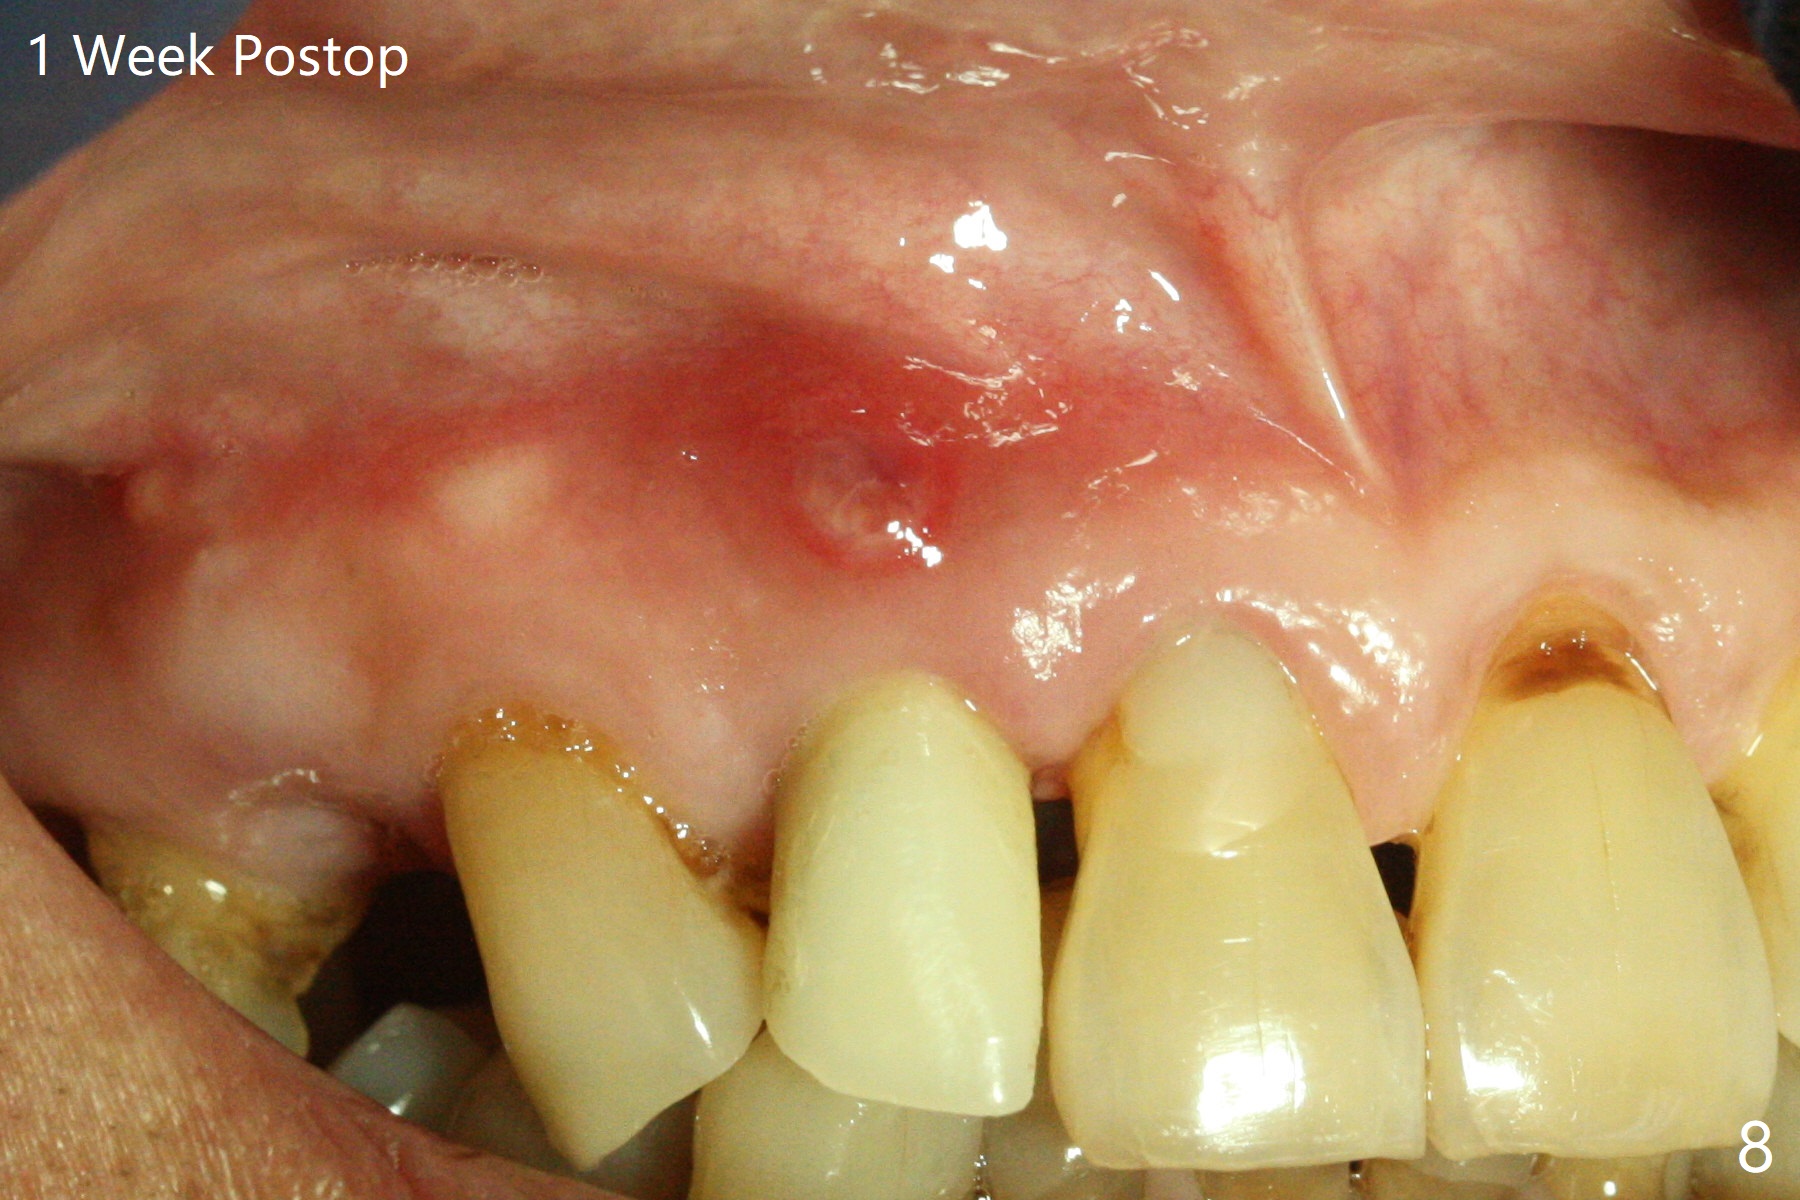

An apical abscess is present when the patient returns for immediate implant at #7 (Fig.1 *); a 2nd challenge is deep bite. After smooth extraction, the apical buccal plate is found to be perforated. Following debridement, a piece of gauze is placed in the apical defect for hemostasis, while osteotomy is initiated palatal (Fig.2). The apical defect seems to be extensive (Fig.3 yellow dashed line). A new trajectory is intended (red arrow) without much success. Before implant placement, bone graft is placed in the apical defect defect area, while a drill (Fig.4 D) is inserted in the finished osteotomy (Fig.5 O). In spite of seemingly large apical defect, the buccal crest bone exists (Fig.4 x). A 3x14(2) mm 1-piece implant is placed with stability; the first round of bone graft is apparently around the apical portion of the implant (Fig.6 *). The coronal end of the implant has to be adjusted several times buccopalatally to accommodate the deep bite. A 2nd round of bone graft following an immediate provisional closes the coronal space of the socket (Fig.7 *). CT will be taken to show the bone graft to repair the buccal plate defect when the patient returns for postop follow-up. In fact the defect is minimal in CT a month ago. The fistula does not disappear 1 week postop, but it is non tender (Fig.8). The patient complains of asymptomatic swelling in the right nostril. CT shows that the large buccal perforation is repaired with large amount of bone graft (Fig.9,10 *). It would be nicer to place the implant slightly more buccal apically (Fig.11 red lines; Fig.12 (preop design)). The buccoapical fistula disappears nearly 1 month postop (Fig.13). The apparently "lifeless" bone graft seems to be harmonious with the surrounding tissue (Fig.14). The periimplant gap reopens with implant mobility nearly 4 months postop (Fig.15), which is related to micro-movement associated with the immediate provisional. The latter is removed. A larger 2-piece implant will be placed in a 2-staged manner if needed (Fig.16). In fact the 3x14 mm straight 1-piece implant (Fig.17) has no mobility when it is retightened, but the trajectory remains buccal. Incision shows that there is no implant thread exposure. A 3x14 mm 15 degree angled 1-piece dummy implant is able to establish the correct trajectory, but there is no occlusal clearance (Fig.18). Micromovement during osteointegration may recreate loosening. Finally using Lindamann bur, the osteotomy is changed so that a 3.5x13 mm 2-piece implant does not need an angled abutment to establish occlusion (Fig.19). There is one palatal thread exposure. Allograft is placed circumferentially, followed by Human Amnion-Chorion Allograft and Collagen Plug. The wound does not heal 8 days postop (Fig.20), as related to the age (79 years old)? The wound appears to heal with a membrane on the surface (Amnion-Chorion one?) 3 weeks postop (Fig.21). The ridge looks wide 3.5 months postop (Fig.22,23). A 4.5x5.5(3) mm appears to be seated incompletely with a gap between the abutment and the implant (Fig.24<). A provisional is fabricated after heavy palatal reduction. Two months later, the provisional fractures. After repositioning the abutment with complete seating and torque (Fig.25), impression is taken. Although the buccal plate is concave, the gingiva remains healthy 10 months post cementation (Fig.26,27).